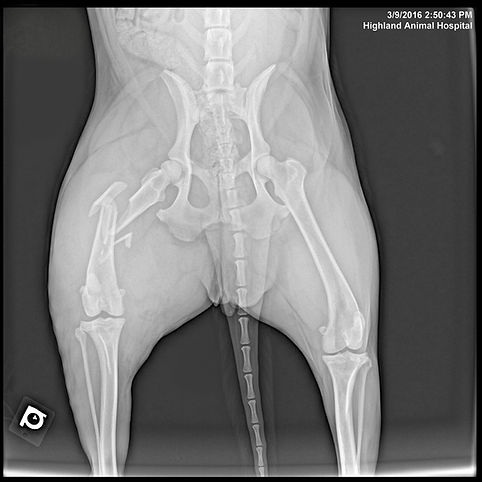

Pre-op Femoral Fracture

Post-Op Femoral Repair

Bone fracture – $1,600-3,500

Femoral head osteotomy (FHO) – $1,650-2,650